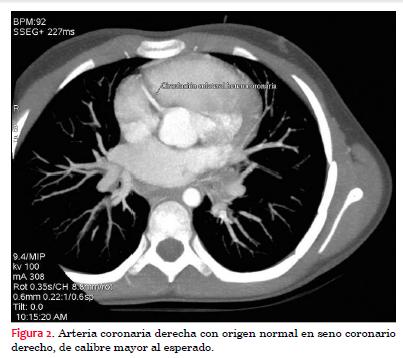

Se realiza tomografía multicorte. Adquisición en equipo General Electric de 64 receptores Lightspeed VCT con la paciente bajo anestesia general, con gating retrospectivo y con contraste intravenoso: iopromida 370 mg I/ml, utilizando un total de 20 ml bajo anestesia general inhalatoria y sin betabloqueo. Frecuencia cardíaca: 180 lpm. La buena calidad de la imagen obtenida se debe a dos aspectos: se utilizó un protocolo para frecuencias cardíacas elevadas para uso pediátrico y el pequeño tamaño corporal. No se hizo volume rendering porque a esa frecuencia cardíaca la imagen es de pésima calidad para esa técnica, no así para la imagen angiográfica. Se hace diagnóstico anatómico de origen anómalo de arteria coronaria izquierda en arteria pulmonar (figuras 2, 3, 4 y 5).

El diagnóstico se confirmó mediante aortografía y coronariografía selectiva de arteria coronaria derecha, realizadas bajo anestesia general, mediante angiógrafo Phillips Integris BH 3000, biplano, utilizando como contraste intravenoso iopromida 300 mg I/ml, utilizando 12 ml (figuras 6, 7 y 8).